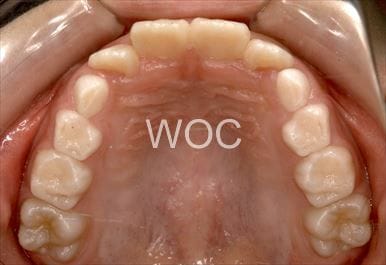

治療後1

治療後2

治療後3

治療後4

治療後5

- 年齢:23歳女性

- 主訴:出っ歯、口が閉じにくい

- 基本矯正料金:895,000円

- 治療期間:1年10ヶ月

- 非抜歯